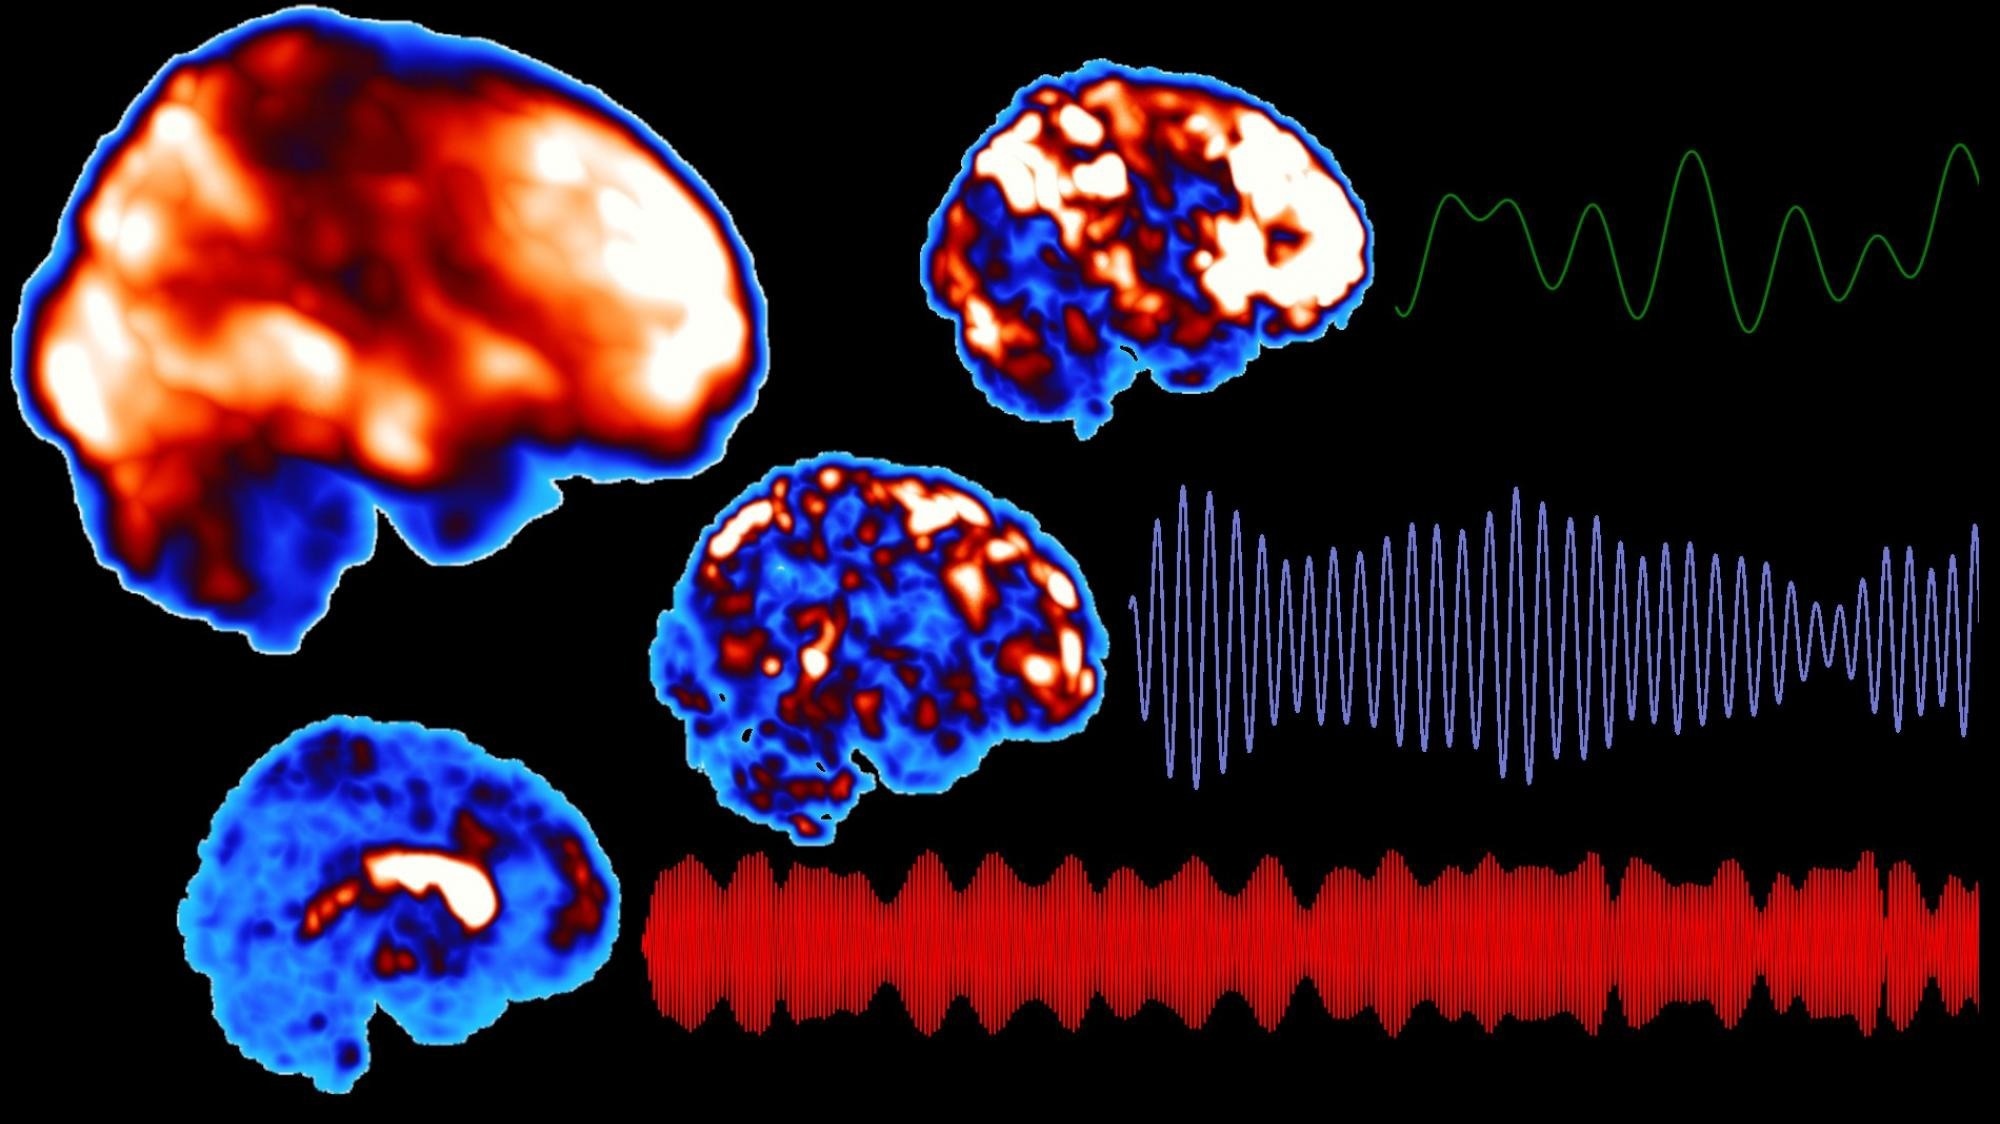

The research method is based on fast functional magnetic resonance imaging of the brain, which allows the signals representing pulsations to be extracted from the raw signal. Image Credit: University of Oulu

Three types of pulsations are associated with brain clearance: cardiovascular pulsations of the brain arteries produced by the heartbeat, respiratory pulsations of the veins and cerebrospinal fluid, and slow vasomotor fluctuation of the vessel walls. The study showed that people with narcolepsy experience changes in all three types of brain pulsation.

Changes in pulsations were associated with the severity of the disease. Abnormalities in cardiac pulsation in brain regions relevant to narcolepsy were associated with the severity of symptoms experienced by the patient, with lower variability in cardiac pulsation predicting more severe symptoms. According to the researchers, this finding could be useful in optimizing the treatment response to narcolepsy.